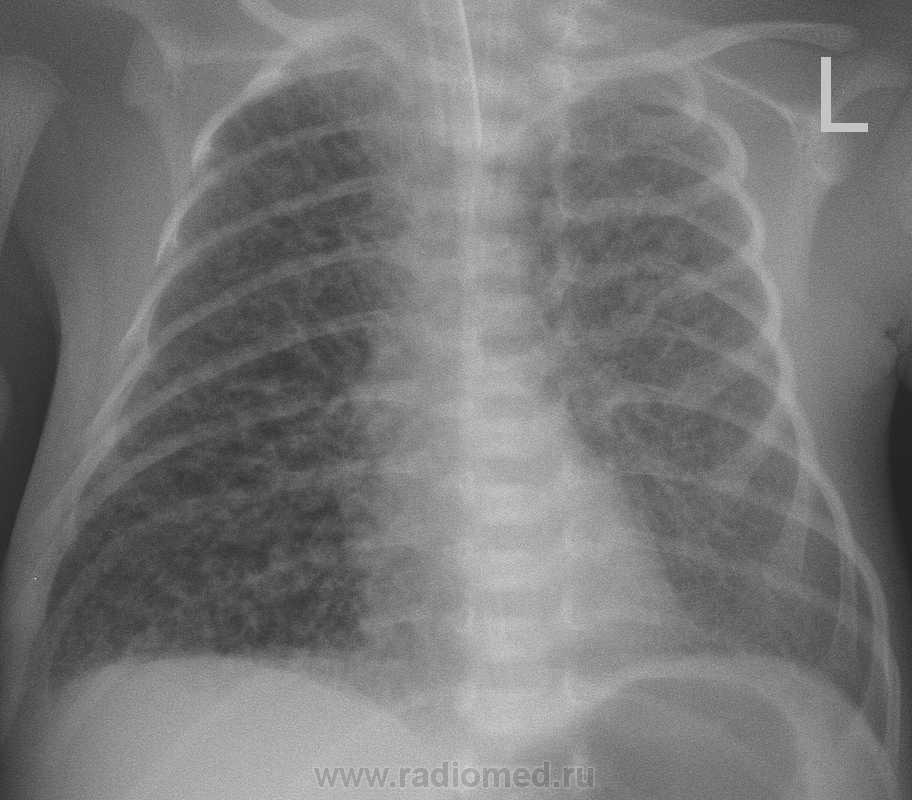

Новорожденный в сроке 30 недель, в данный момент находиться в детской реанимации, к нам сегодня обратился педиатр с просьбой повторно проанализировать обзорную рентген-картину органов грудной клетки. В анамнезе у мамы носительства цитамегаловируса и токсоплазмоза.  На данный момент у меня мысли о наличие генерализованной формы токсоплазмоза у ребенка в легких ввиде сепсиса, возможно я ошибась, возможно у кого имеются другие мысли по данному случаю?

Снимок от 2.03.10г.

Мелкоочаговая мономорфная диссеминация.

Трудно сказать, но мысли в пользу интерстециальной пневмонии, преимущественно вирусной этилогии, однако ребенку провели курс антибактериальной терапии, на данный момент он самостоятельно дышит, клиники ни какой нет, динамика положительная. Во время прведения курса лечения 9.03. был сделан рентген-контроль, где  динамика положительная была.

1.По диссеминации похоже динамика положительная.

2.Но не складывается ли впечатление о появлении сливной инфильтрации справа в базально-медиальном отделе, ближе к корню?

3.В нерешительностиВозможно присоединение бактериального компонента на фоне вирусного поражения....